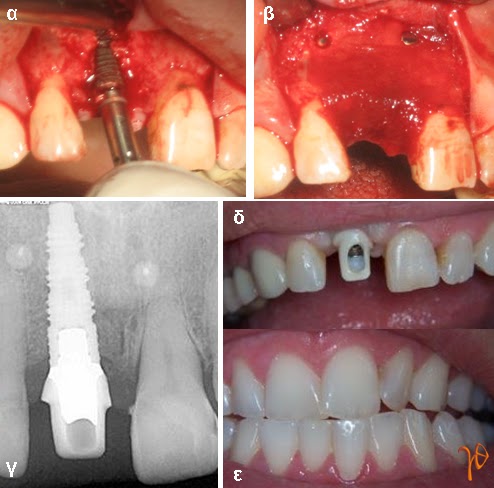

Εικόνα 1.2: (α) τοποθέτηση νέου εμφυτεύματος στη θέση #11, (β) τοποθέτηση οστικού μοσχεύματος και μεμβράνης με pins (γ) οπισθοφατνιακή ακτινογραφία μετά από τέσσερεις μήνες, (δ) και (ε) μόνιμη προσθετική αποκατάσταση #11.